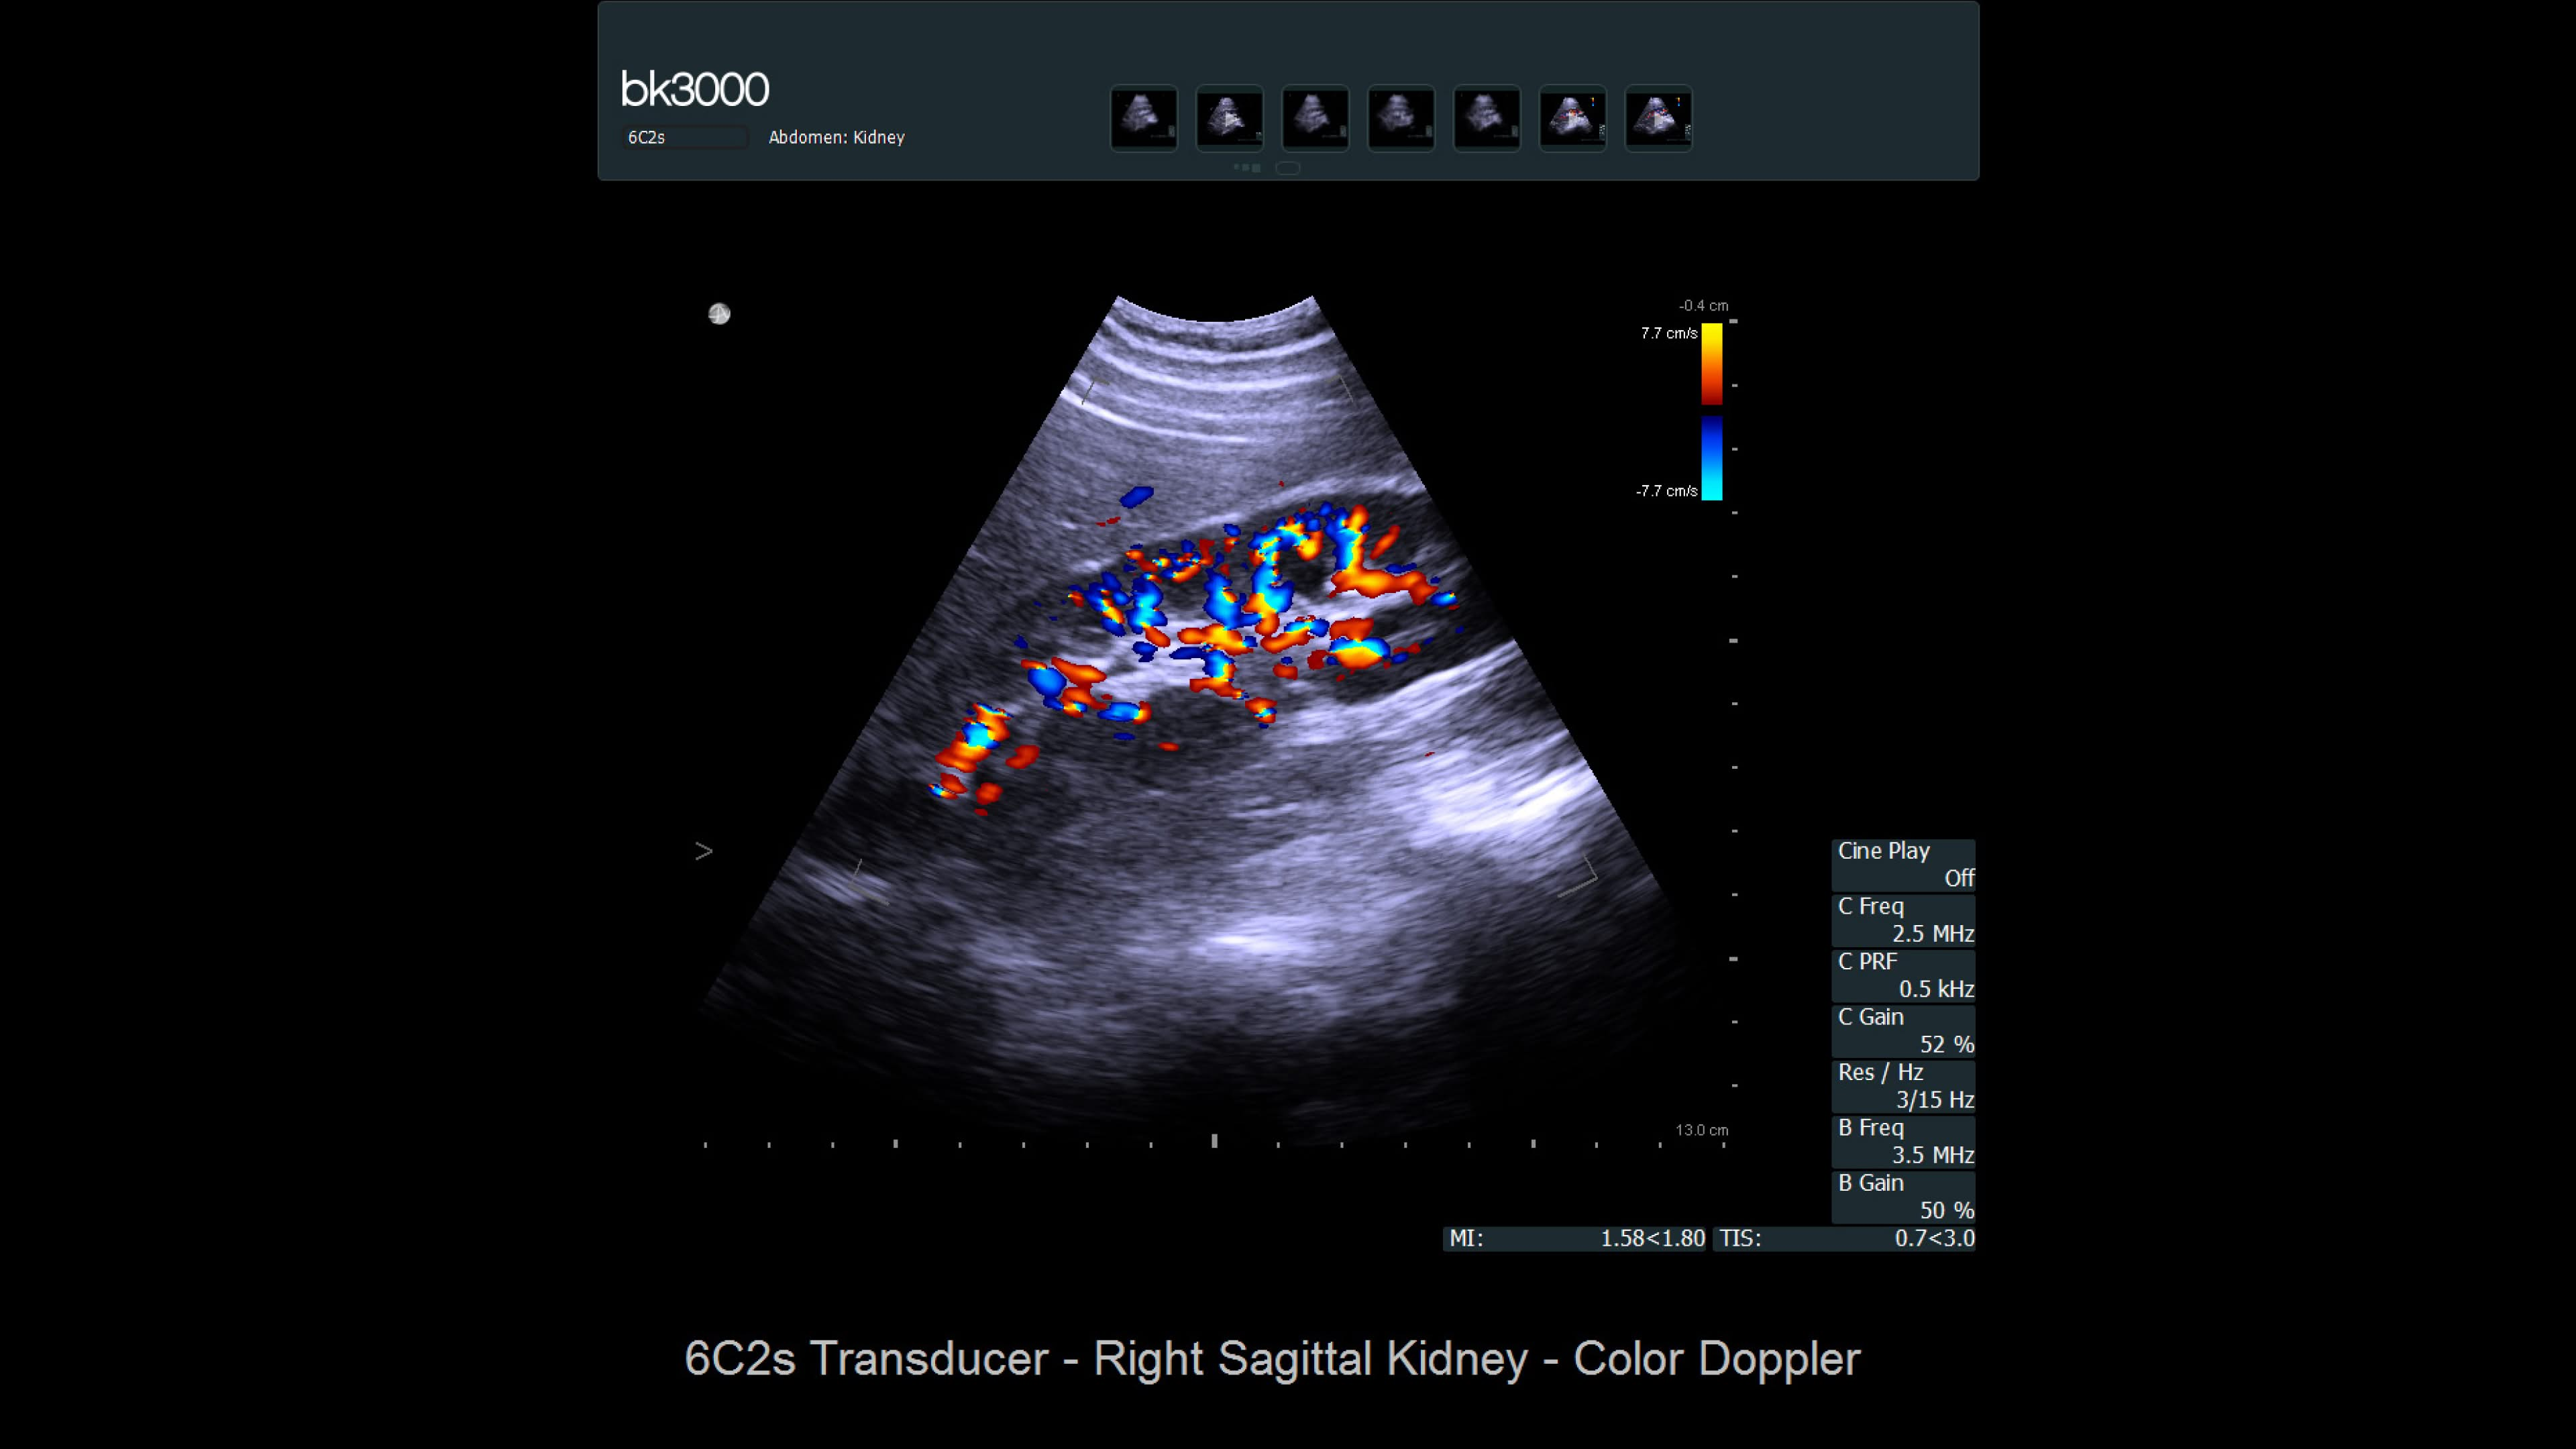

Ultrasound for kidney

Ultrasound provides detailed information for kidney imaging, measurement, and biopsies. The bk3000 and bkSpecto systems help visualize fine anatomical details, see vascularization, measure blood flow, and locate kidney stones. The bkActiv, our flagship system, offers next-level imaging for prostate, renal, kidney, and bladder imaging, with sensitive Doppler for blood flow. Combined with sterilizable transducers, the bkActiv sets a new standard for surgical urology.